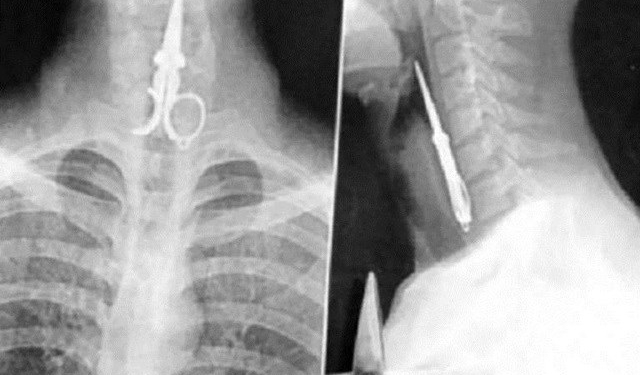

6. Uma briga resultou nessa tesourada. O homem, por sorte, não teve nenhuma região vital atingida e se recuperou bem.

7. Essa pessoa achou que daria tudo certo palitar os dentes com uma tesoura. Como vemos, foi um engano.